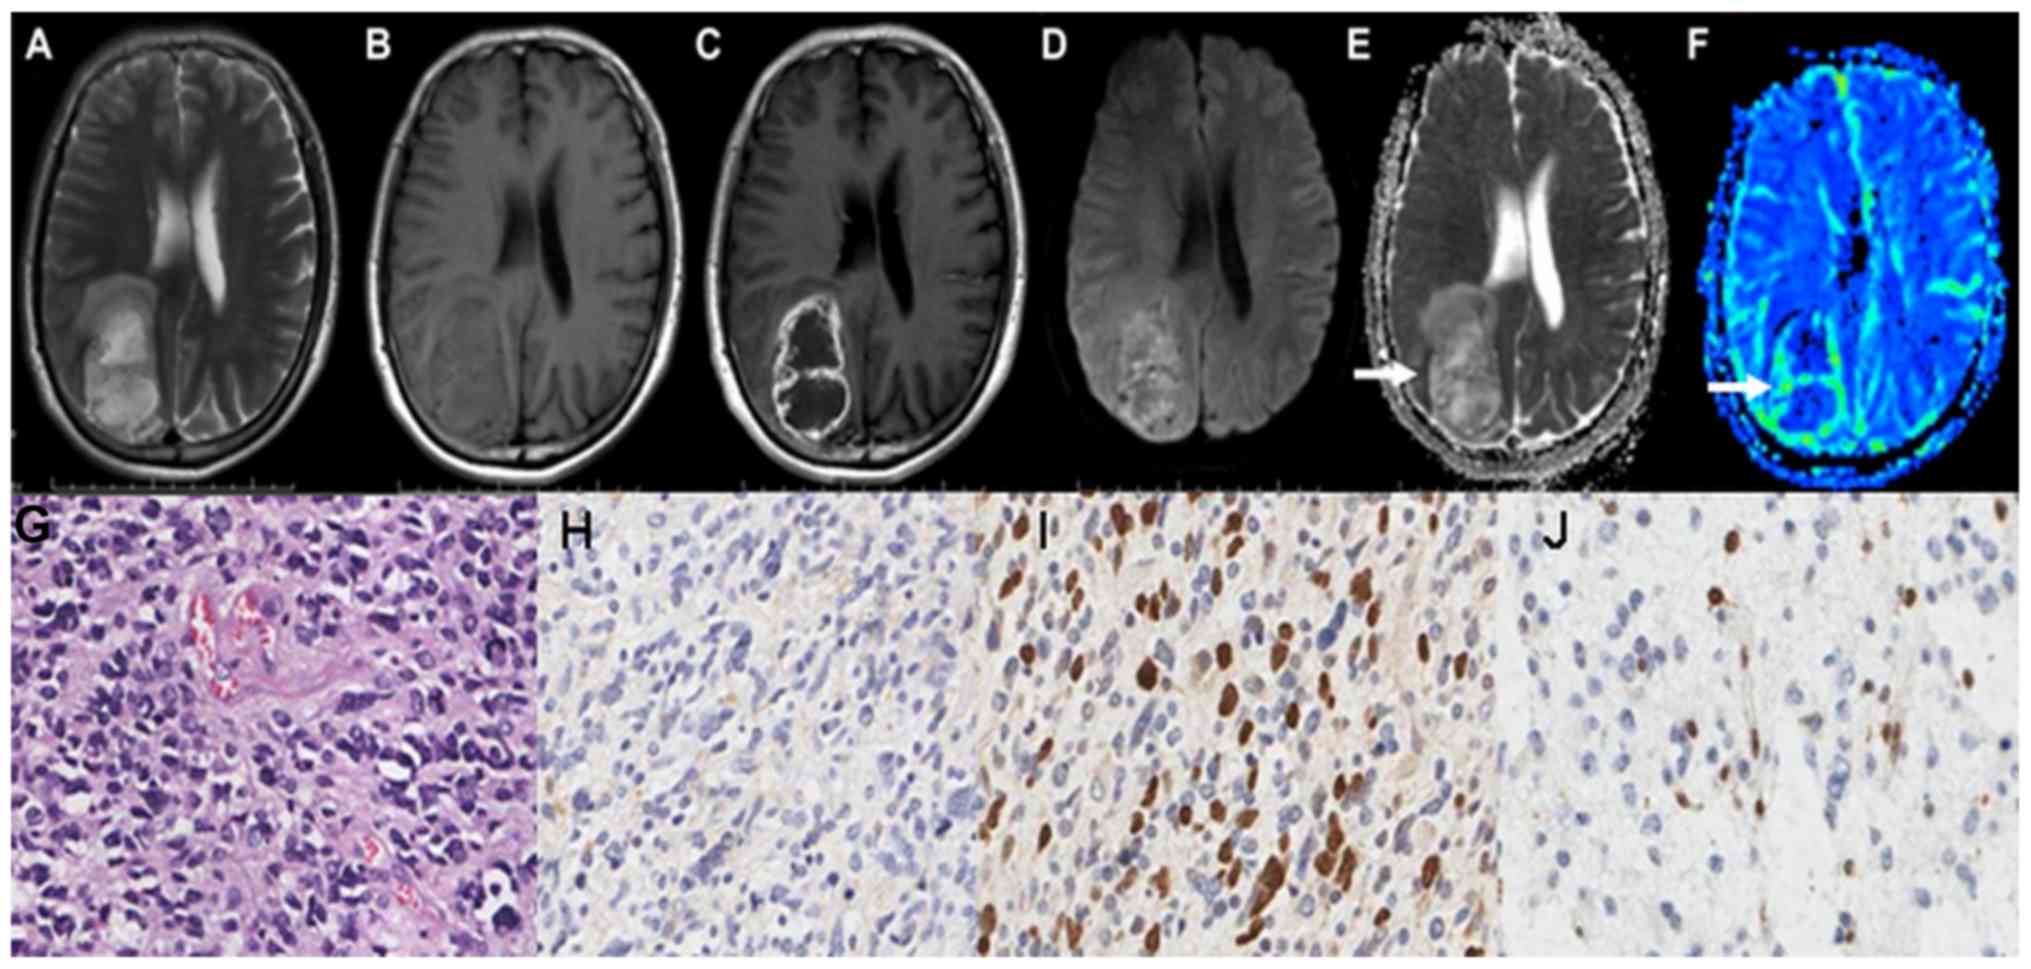

The maps of the aforementioned conventional MRI scans of grade II astrocytoma are demonstrated in Fig. 1A-C. Grade II astrocytoma exhibited low signal on DWI sequence, and high ADC values, as illustrated in Fig. 1D and E. The parenchyma of grades II astrocytoma on the rCBV maps exhibited low signals, as illustrated in Fig. 1F-J demonstrate the HE staining map, IHC. GFAP map, IHC. Topo IIα map and IHC. MGMT map of grades II astrocytoma respectively. The conventional MRI scans of grade III astrocytoma are demonstrated in Fig. 2A-C. Grade III astrocytoma demonstrated high signal on DWI sequence, and the ADC values of the tumor parenchyma were lower, as illustrated in Fig. 2D and E. The parenchyma of grades III astrocytoma on the rCBV maps exhibited high signals, as illustrated in Fig. 2F-J demonstrate the HE staining map, IHC. GFAP map, IHC. Topo IIα map and IHC. MGMT map of grades III astrocytoma respectively. The conventional MRI scans of grade IV astrocytoma are demonstrated in Fig. 3A-C. Grade IV astrocytoma demonstrated the highest signal on the DWI maps, and the ADC values were the lowest between all of the astrocytoma grades, as illustrated in Fig. 3D and E. The grade IV astrocytoma on the rCBV map demonstrated the highest signal, as illustrated in Fig. 3F-J demonstrate the HE staining map, IHC. GFAP map, IHC. Topo IIα map and IHC. MGMT map of grades IV astrocytoma respectively.

Figure 2.

Right frontal lobe anaplastic astrocytoma (Grade III) in a 43-year-old female patient. (A) The right frontal lobe lesion exhibited a phymatoid isointense signal on T1 and (B) T2 WI. (C) Axial contrast-enhanced T1 WI revealed mild to moderate enhancement. (D) Lesions exhibited a hyper-intense signal on diffusion-weighted imaging map. (E) The apparent diffusion coefficient map displayed low signal in the tumor parenchyma (arrow). (F) The relative cerebral blood volume value was high in the tumor parenchyma (arrow). (G) hematoxylin and eosin staining map revealed moderately differentiated tumor cells with nuclear atypia. (H) Moderate glial fibrillary acidic protein expression level in the cytoplasm. (I) Moderate expression level of topoisomerase IIα in the nucleus. (J) The O 6-methylguanine-DNA methyltransferase proteins demonstrated a low to moderate expression level in the cytoplasm and nucleus. WI, weighted image.